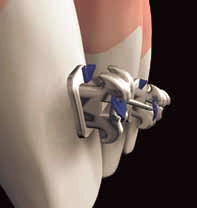

With two placement options available to you, placing No•Trace brackets and archwires, is a simple process. Remarkably similar to a typical labial procedure it typically requires about 30 minutes of chair time to complete.

Direct Placement

Direct placement of No•Trace brackets requires 3 easy steps. First, prep the teeth as you would for normal labial bonding. Second, apply adhesive and position brackets 1-2mm from the incisal edge and cure. Once the brackets are completely cured, the archwire can be immediately inserted in to the self-ligating No•Trace brackets, using thumb pressure to close the clip and secure the wire in the same manner as labial self-ligating brackets.